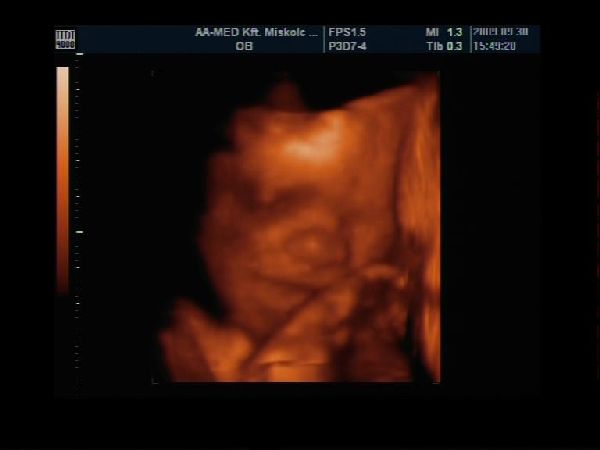

Van egy pár percem a gép előtt, gyorsan teszek fel Nektek képecskéket :wink:

Szerintem olyan szép pofija van és természetesen nekem Ő a legszebb :lol: :lol: :lol:

Szerencsére szépen mutatta magát, láttuk mindenét, most már biztos, hogy cunis :lol:

Apa is nagyon élvezte, főleg, hogy ennyire jól lehetett látni a kis tündérkénket :D

A képek 27 hetese és 1 napos: Kép Kép Kép Kép

Akella, ez egy gyönyörűség, ahogy mosolyog, meg cuclizza az ujjacskáját, olyan cuki :D . Istenem, de rég volt, hogy ilyen képeket nézegettünk UH-on. :|